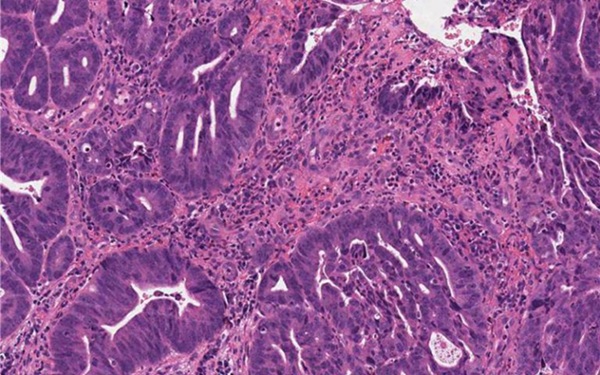

- AI Pathology Analysis System Delivers Comprehensive Cancer Diagnosis